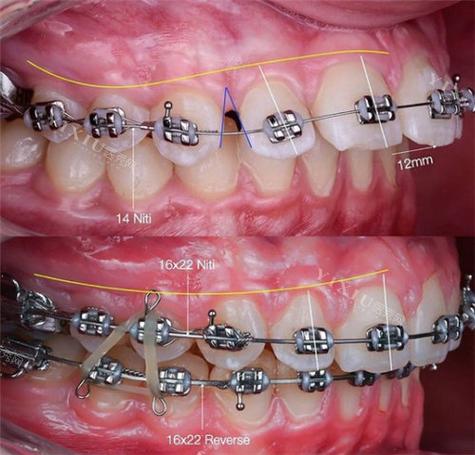

在临床应用中,圣马特托槽的核心优势主要体现在三个方面,首先是摩擦力的显著降低,传统托槽依赖结扎丝或橡皮圈固定弓丝,易产生较大摩擦阻力,而圣马特托槽的锁闭机制使弓丝与托槽槽沟的接触面积增大、压力分布更均匀,摩擦系数可降低至传统托槽的1/3-1/2,这意味着牙齿在移动过程中受到的阻力更小,移动效率更高,尤其适合解决牙齿拥挤、扭转等问题,有助于缩短治疗周期(通常可缩短3-6个月),其次是口腔卫生维护的便捷性,自锁托槽没有结扎丝等突出结构,食物残渣不易堆积,患者刷牙、使用牙线时更方便清洁,降低了正畸期间牙龈炎、龋齿等并发症的风险,最后是治疗舒适度的提升,由于无需频繁更换结扎丝,复诊时的操作时间缩短,且弓丝对牙齿的持续轻力作用减少了疼痛感,尤其适合对疼痛敏感或配合度较低的患者。